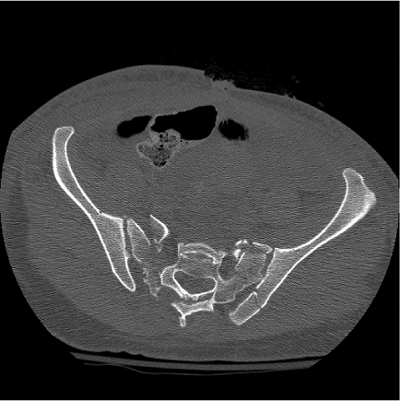

|

Figure 40.16. Axial CT scan demonstrating comminuted zone II sacral fractures as well as a PSIS fracture-dislocation component on the left.